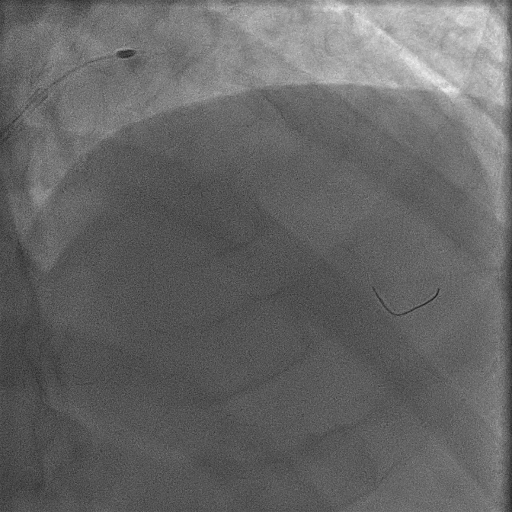

Coronary angiography demonstrated a sharp, heavily calcified protrusion in the distal left main artery, with contiguous calcification involving the LCX ostium and producing significant luminal stenosis. An intravascular ultrasound (IVUS) examination was attempted to better characterize the plaque morphology; however, the IVUS catheter could not be advanced across the left main lesion.

LAO caudal.mp4

Calcification to the LCX_AP caudal.mp4